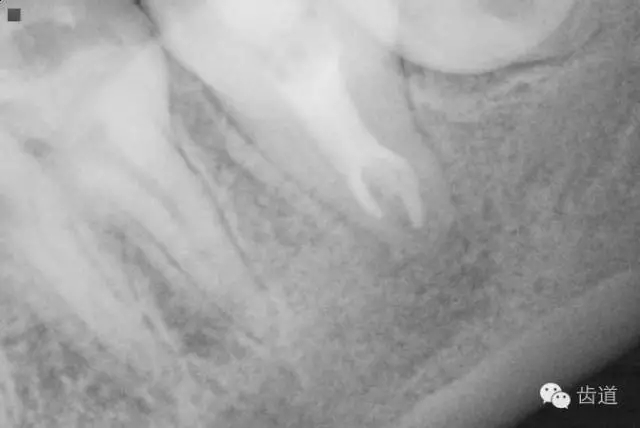

1. 術(shù)后半年口內(nèi)照片

2. 術(shù)后半年X線檢查,可見根尖周膜連續(xù)性恢復(fù),根尖周透射影消失